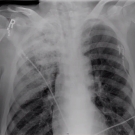

A 60-year-old woman presented to the emergency department with blunt thoracic trauma after a head-on motor vehicle accident.